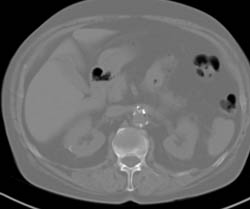

Diagnosis

Normal Vascular Anatomy of the Foot